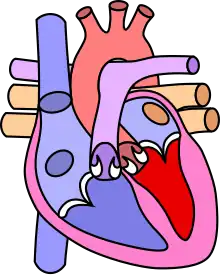

Four malformations

"Tetralogy" denotes four parts, here implying the syndrome's four anatomic defects.[2] This is not to be confused with the similarly named teratology, a field of medicine concerned with abnormal development and congenital malformations (including tetralogy of Fallot). Below are the four heart malformations that present together in tetralogy of Fallot:

| Pulmonary Infundibular Stenosis | A narrowing of the right ventricular outflow tract. It can occur at the pulmonary valve (valvular stenosis) or just below the pulmonary valve (infundibular stenosis).[4] Infundibular pulmonic stenosis is mostly caused by the overgrowth of the heart muscle wall (hypertrophy of the septoparietal trabeculae),[41] however, the events leading to the formation of the overriding aorta are also believed to be a cause. The pulmonic stenosis is the major cause of the malformations, with the other associated malformations acting as compensatory mechanisms to the pulmonic stenosis.[42] The degree of stenosis varies between individuals with TOF and is the primary determinant of symptoms and severity. This malformation is infrequently described as sub-pulmonary stenosis or subpulmonary obstruction.[43] |

| Overriding aorta | An aortic valve with biventricular connection, that is, it is situated above the ventricular septal defect and connected to both the right and the left ventricle. The degree to which the aorta is attached to the right ventricle is referred to as its degree of "override." The aortic root can be displaced toward the front (anteriorly) or directly above the septal defect, but it is always abnormally located to the right of the root of the pulmonary artery. The degree of override is extremely variable, with 5-95% of the valve being connected to the right ventricle.[41] |

| Ventricular septal defect (VSD) | A hole between the two bottom chambers (ventricles) of the heart. The defect is centered around the most superior aspect of the ventricular septum (the outlet septum), and in the majority of cases is single and large. In some cases, thickening of the septum (septal hypertrophy) can narrow the margins of the defect.[41] |

| Right ventricular hypertrophy | The right ventricle is more muscular than normal, causing a characteristic boot-shaped (coeur-en-sabot) appearance as seen by chest X-ray. Due to the misarrangement of the external ventricular septum, the right ventricular wall increases in size to deal with the increased obstruction to the right outflow tract. This feature is now generally agreed to be a secondary anomaly, as the level of hypertrophy tends to increase with age.[44] |

There is anatomic variation between the hearts of individuals with tetralogy of Fallot.[10] Primarily, the degree of right ventricular outflow tract obstruction varies between patients and generally determines clinical symptoms and disease progression.[10]

Presumably, this arises from an unequal growth of the aorticopulmonary septum (aka pulmonary outflow septum).[20]: 199 The aorta is too large, thus "overriding," and this "steals" from the pulmonary artery, which is therefore stenosed. This then prevents ventricular wall closure, therefore VSD, and this increases the pressures on the right side, and so the R ventricle becomes bigger to handle the work.[20]: 199